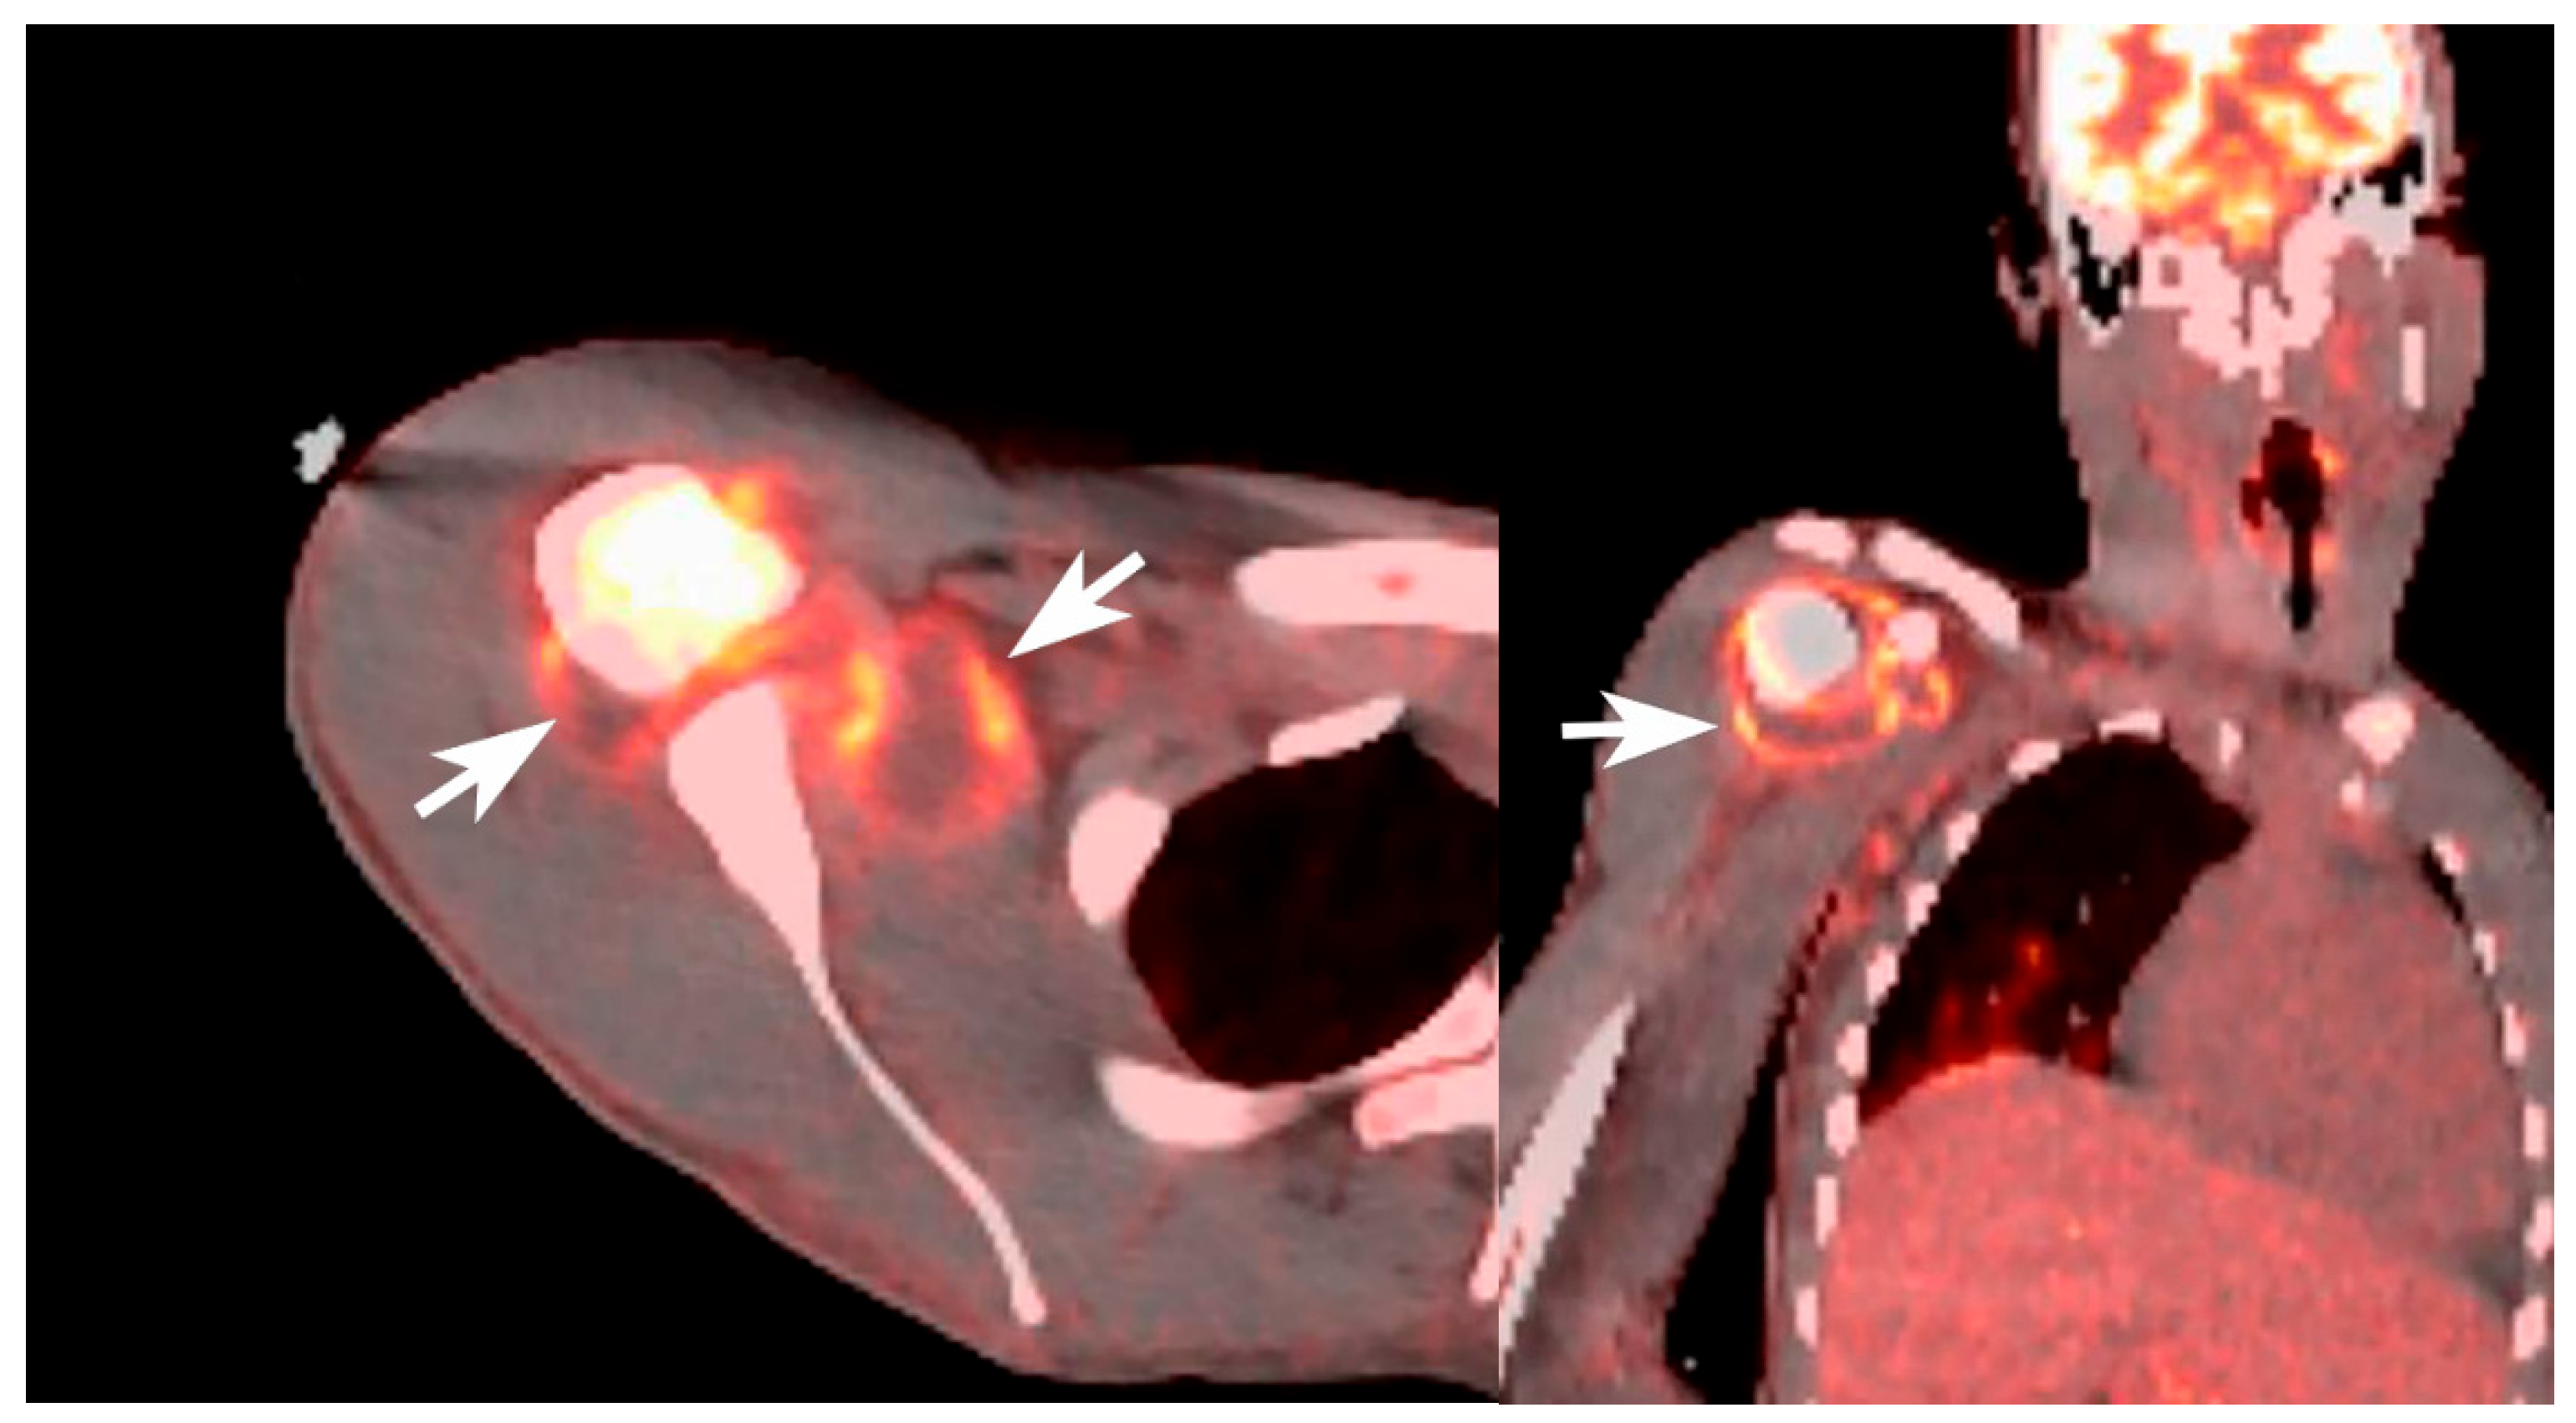

| 1 December | 7–8 | Whole-body PET-CT demonstrated hypermetabolic activity in the proximal right humerus with adjacent shoulder fluid collection. |

| 2 December | 9 | Ultrasound-guided arthrocentesis of the right shoulder performed; synovial fluid cultures grew Salmonella species. |